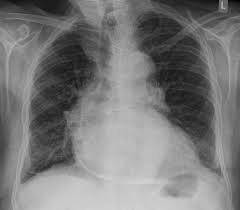

- 호흡 곤란: 심낭 주위의 염증으로 인해 심장의 움직임이 제한되거나 심낭액이 증가할 경우, 호흡이 어려울 수 있습니다. 특히 심낭액이 증가하면 폐의 움직임을 방해할 수 있습니다.

2. 심낭액 배출 시술

- 심낭액이 과도하게 증가하여 호흡이나 심장 기능에 영향을 미치는 경우, 심낭액을 배출하는 시술을 고려할 수 있습니다. 이는 심낭액의 압력을 줄여 호흡과 심장 기능을 개선하는데 도움을 줄 수 있습니다.